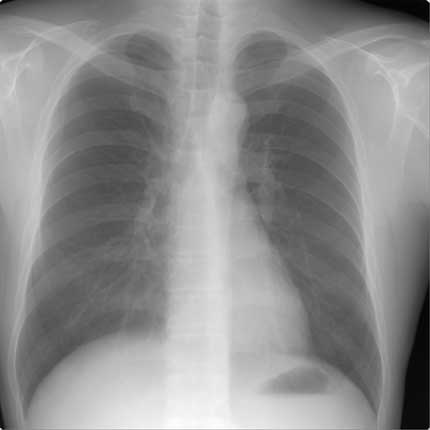

Example of a real "Normal Lung" of a 40-year old male:

When you compare this to the example of a real normal one above, you can see how

the right side it shifted up and the upper right area is not as dark.

The dark area indicates "air" in the lung (when you get a chest x-ray they ask

you to breath in deep). Also note on the left hand side you see more of a

full lung, remembering that the heart is in front of the lung on that side so it

does not show up as dark.

But you can tell something is not quite right with the right lung presentation.

Nonetheless, the Solantic doctor indicated it as "normal

lung".